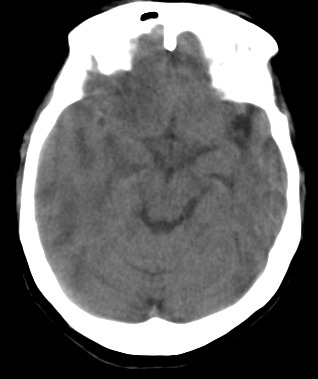

周*,女,78岁,阵发性意识障碍月余,查体四肢肌张力可,病理反射未引出。有脑哽塞病史

右颞顶枕叶多发低密度影,同侧脑室受压变形,病变有明显占位效应.考虑脑肿瘤性病变,建议增强!!!

影像表现: 右侧额、颞、顶叶多发等、低密度区,部分呈结节灶,灶周有不同程度水肿,散在发生,占位效应较重,感觉不是一个整体性病灶,病灶形态呈不规则状明显不同于mca供血区梗死,病变累及基底节区白质。

诊断:右侧额、颞、顶叶肿瘤性病变,首先考虑转移瘤。建议胸片。需与胶质瘤、mca供血区梗死以及脱髓鞘改变区别。

右侧颞,顶叶水肿呈指状,右额叶可见条形低密度带,右侧脑室明显受压,支持右侧脑实质多发转移瘤,建议增强,或拍胸部x片。

右颞顶枕叶多发低密度影,同侧脑室受压变形,病变有明显占位效应,建议增强.

病灶周围脑实质受压明显,右侧脑室受压变形,脑沟明显变浅。支持脑内肿瘤的第一诊断,(不知病人曾经的脑梗塞是否诊断明确),其次考虑脑梗塞的诊断(看起来不大像)

病史:女,78岁,阵发性意识障碍月余,查体四肢肌张力可,病理反射未引出。可基本除外缺血性病变。[br]影像表现: 右侧额、颞、顶叶多发等、低密度区,部分呈结节灶,灶周有不同程度水肿,散在发生,占位效应较重,感觉不是一个整体性病灶,病灶形态呈不规则状明显不同于mca供血区梗死,病变累及基底节区白质。[br]诊断:右侧额、颞、顶叶肿瘤性病变,首先考虑转移瘤。建议胸片。需与胶质瘤、mca供血区梗死以及脱髓鞘改变区别。

右侧额叶大片状水肿,呈指状改变,周围脑沟脑裂消失,右侧脑室受压缩小,提示占位效应明显,平扫未见明显瘤体,单纯从ct片上看可考虑肿瘤,转移瘤或胶质瘤,建议mri检查,以明确诊断.

右侧额、颞、顶叶多发不同程度低密度水肿区,可见占位效应

首先考虑右侧额、颞、顶叶肿瘤性病变,转移瘤可能性大。(部分病灶可能是梗塞性改变)